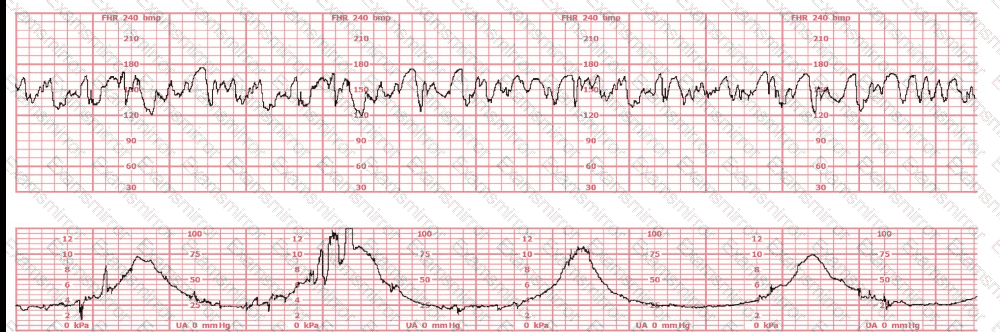

The baseline fetal heart rate in this tracing is:

What is the appropriate interpretation of this tracing?